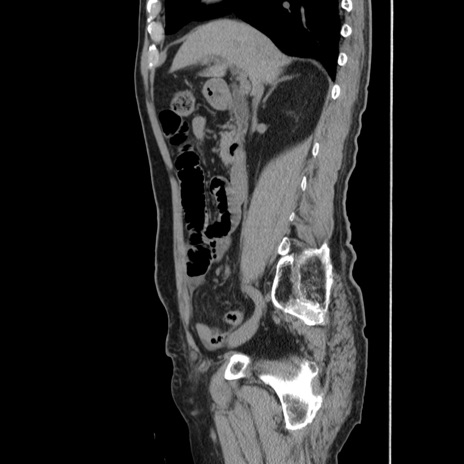

症例24(矢状断像)

【症例】80歳代男性

【主訴】左側腹部痛、嘔吐

【現病歴】本日早朝より左腹部に痛みあり。昼頃嘔吐認めたため、救急要請。

【既往歴】直腸癌(Mile手術)、胆摘

【身体所見】意識清明、BT 35.9℃、BP 221/93mmHg、SpO2 97%(RA) 、腹部:左ストーマ周囲に限局性の腹部膨隆あり。 膨隆部自発痛・圧痛あり・軟。

【データ】WBC 7700、CRP 0.09